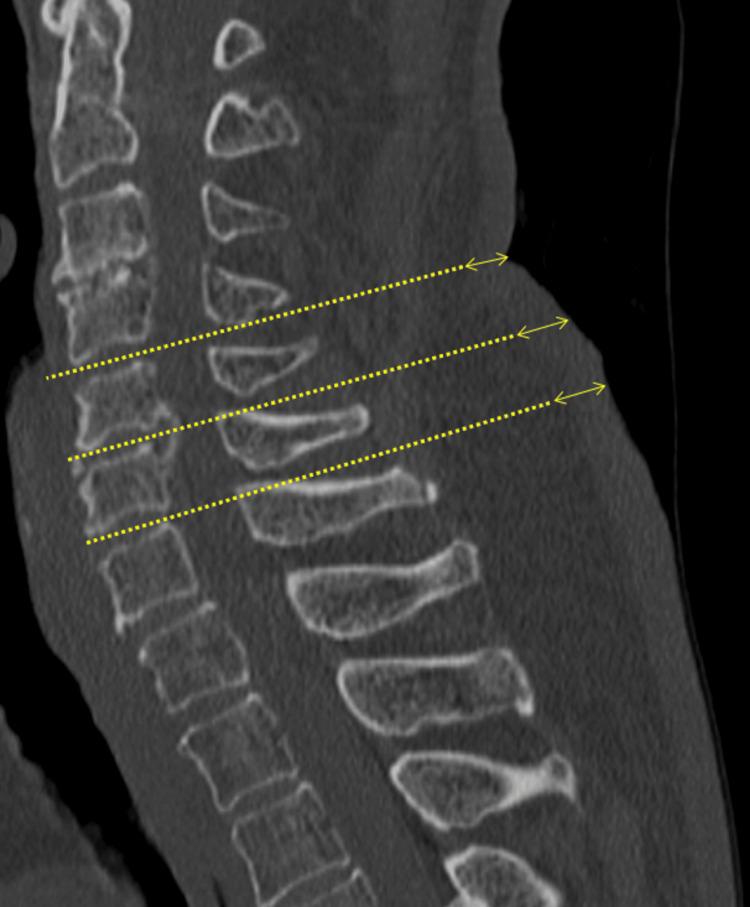

这项回顾性队列研究纳入了2022年1月至2023年3月期间在我院接受脊柱手术治疗的99例年龄≥60岁的连续患者。在全脊柱CT矢状面图像上测量颈椎、胸椎和腰椎椎体背侧的皮肤厚度。根据中位数,将皮肤厚度以4mm的中位数为界分为两组。评估骨密度(BMD)。将前纵韧带和后纵韧带的椎体及椎间桥接骨赘总和定义为OALL指数和OPLL指数。测量血清骨代谢相关标志物水平,如抗酒石酸酸性磷酸酶5b、前胶原I N端前肽、25-羟基维生素D和骨膜蛋白。为评估皮肤厚度与影像学表现之间的关联,我们计算了调整后的比值比,对年龄、性别和体重指数(BMI)进行了校正,并使用单因素和多因素逻辑回归分析。

结果

颈椎、胸椎和腰椎三个背侧区域的皮肤厚度(中位数分别为3.3mm、3.5mm和3.4mm,p = 0.357)以及骨代谢相关标志物之间未发现显著差异。校正年龄、性别和BMI后,颈椎、胸椎和腰椎皮肤厚度分别与DISH、OPLL指数以及OPLL和OPLL指数相关。